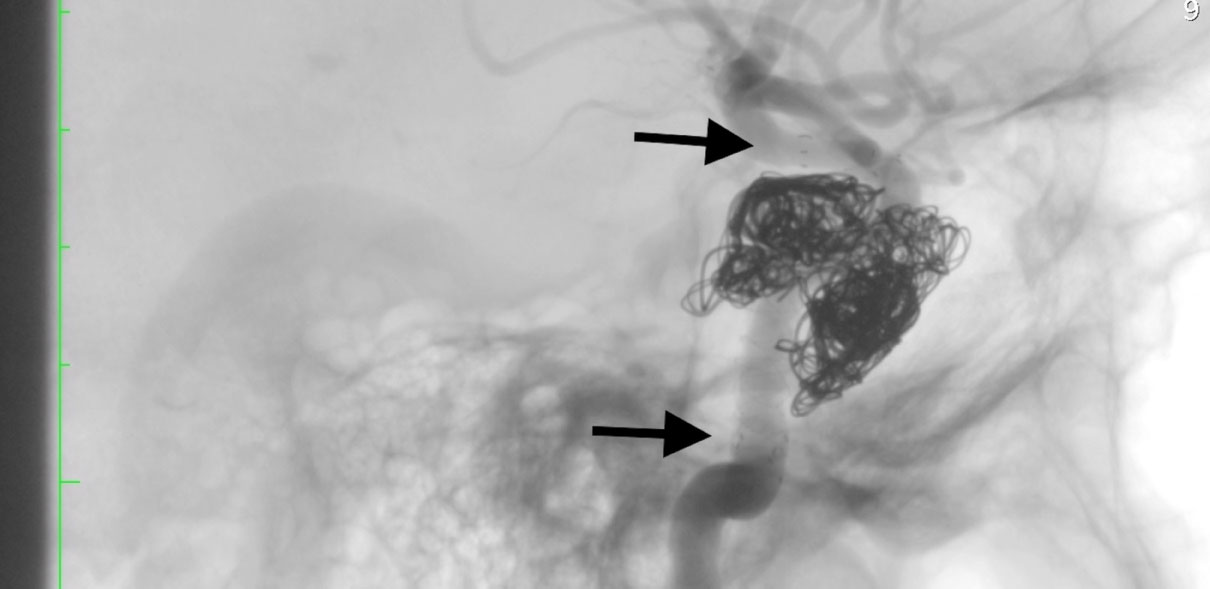

On control angiography, the complete restoration of the ICA lumen with no discharge into the cavernous sinus is determined, the main and distal vessels are passable (Figures 3 and Figure 4). Microcatheter removed without technical difficulties. Endovascular instrumentation removed. Hemostasis, bleeding. A pressure bandage was applied to the puncture site.

Figure 3: Cerebral angiography, lateral projection, Sighted angiography of the right ICA. Embolized section of CCF with implanted flow-diverter sterns. View Figure 3

Figure 4: Cerebral angiography, lateral projection, Arterial phase. Fully restored blood flow in the right ICA. View Figure 4